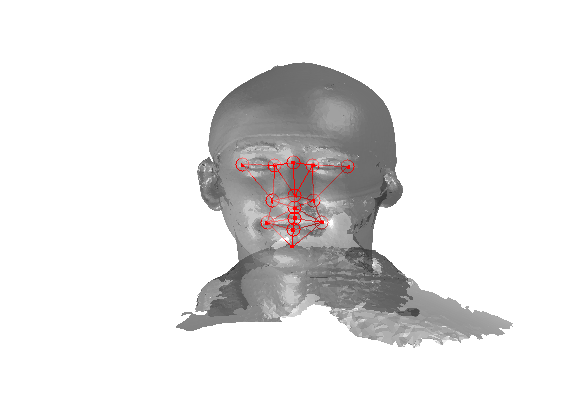

The landmarking system that we have implemented is a modified version of Creusot et al [23], where landmark candidates are generated via per-landmark scoring functions and then a configural model is iteratively fitted using a sample-consensus scheme. There are two parts to this algorithm: an off-line training scheme, shown in Fig. 5 and an online landmarking scheme, shown in 6. Note that we consider a sparse model of the face to consist of a set of landmarks in paticular configuration along with a set of landmark detector functions that score the likelihood of a particular vertex being a particular landmark, based on its local shape.

Referring to Fig. 5, our method is a supervised learning technique - landmarks are marked by hand on a set of training images. We used 279 faces (each different individuals) in the Face Recognition Grand Challenge (FRGC) dataset [26]. The landmarks used are described in table 1 111Some descriptions taken from www.facebase.org and can be seen on an example FRGC 3D face scan in Fig. 7.

Fig. 9 shows examples of the fitted model (trained on FRGC data) on the first four subjects in our Headspace training set. Note that the mean of the landmarks in the sparse model is centred on the orgin, and so the scan data is moved towards that and becomes frontal in pose. We note that other researchers [28] have used 3D landmark localisation to find the head, but often this only includes landmarks that are relatively easy to localise, namely inner eye corners and nose. Localising more landmarks over a wider facial area has a number of advantage in terms of cropping, pose normalisation and global 3D template warping, all of which are described later.